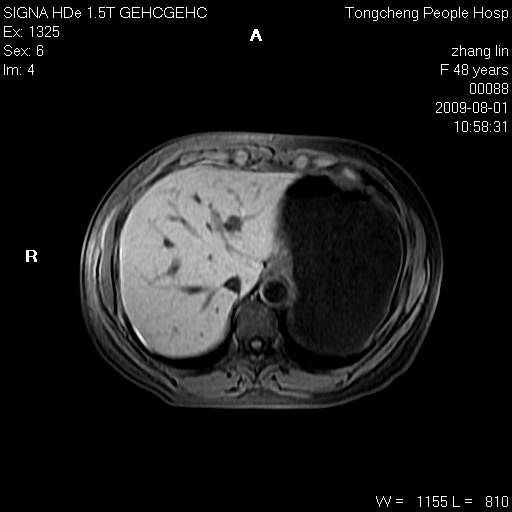

女,48岁。健康体检,彩超发现右肾占位性病变。平素健康。

临床诊断:右肾占位性病变,性质待定(囊肿?肿瘤?)。

上中腹部mr平扫+增强扫描,图像如下:

右肾上极见一类圆形病灶,t1wi呈等信号t2wi呈等高混杂信号,三期增强无强化,边界清---考虑囊肿出血。

同反相位均表现为等信号,病变无强化,考虑含蛋白的囊肿可能,弥散加权相或许有些帮助,

慢性胆囊炎